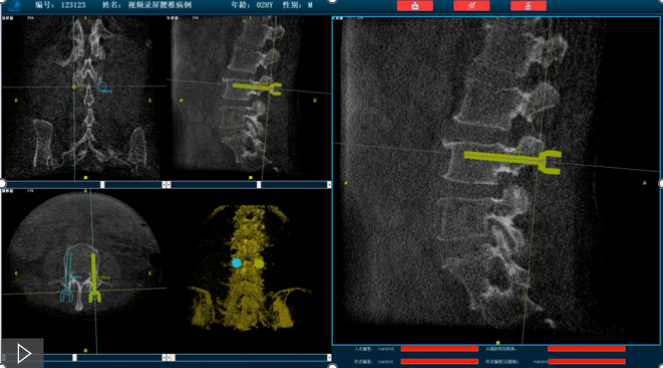

首先,需要明確的是機(jī)器人手術(shù),機(jī)器人在術(shù)中還是做輔助性操作,術(shù)前基于三維C形臂等影像掃描得到骨骼結(jié)構(gòu)的三維數(shù)據(jù),機(jī)器人系統(tǒng)利用手術(shù)規(guī)劃軟件,引導(dǎo)醫(yī)生進(jìn)行可視化預(yù)手術(shù)規(guī)劃(釘?shù)酪?guī)劃、入釘角度),選擇合適的螺釘規(guī)格、尺寸,輔助評(píng)估和及時(shí)調(diào)整手術(shù)路徑規(guī)劃設(shè)計(jì),整臺(tái)手術(shù)都是在主刀醫(yī)生的把控下進(jìn)行操作的。機(jī)器人系統(tǒng)不僅靠譜,而且還提升了手術(shù)的安全性、機(jī)械臂的精準(zhǔn)以及力傳感識(shí)別、實(shí)時(shí)動(dòng)態(tài)追蹤等保護(hù)技術(shù),增加了手術(shù)的準(zhǔn)確性和安全性。

就以普愛醫(yī)療骨科機(jī)器人PL300B為例,骨科機(jī)器人可以保證亞毫米級(jí)精準(zhǔn)度,例如在脊柱上植入椎弓根螺釘,傳統(tǒng)手術(shù)需要暴露骨組織解剖結(jié)構(gòu),往往會(huì)有10-20cm的開口,而使用了手術(shù)機(jī)器人可以將開口轉(zhuǎn)變?yōu)閿?shù)個(gè)1-2cm的開口,出血量降低至95%以上,大大降低并發(fā)癥的發(fā)生率,同時(shí)有益于病患的更快的術(shù)后恢復(fù)。